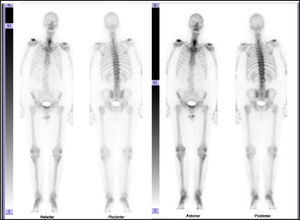

In view of these findings the patient was referred to the nuclear medical unit for a bone scan to rule out several causes of osteoarthritis, Forestier's disease among them.

In the bone scan images there was no sign of articular pathological uptake (Fig. 3). Multimodality SPECT/CT tomographic images were then acquired (Figs. 4 and 5), which were used both for qualitative visual analysis of the sacroiliac joint, and for quantitative analysis which permitted the obtainment of indicators of the sacroiliac-promontory. In visual analysis calcification of the anterior common vertebral ligament was detected, together with absence of sacroiliac uptake. With this information and inferior promontory-sacroiliac indicators below the established cut-off level for diagnosis of sacroiliitis, diagnosis of ankylosing spondylitis was excluded, with support for the diagnosis of Forestier's disease.